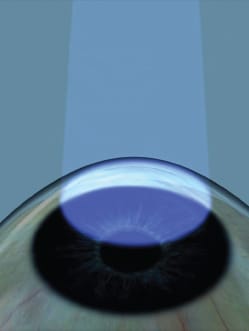

A precisely timed beam of ultraviolet-A light is applied to strengthen mechanical properties of the cornea.

In its simplest terms, CXL first saturates the cornea with riboflavin, followed by the precisely timed application of a beam of UV-A light to strengthen the mechanical properties of the cornea. Avedro, which is expected to dominate the CXL field in the United States when the procedure is approved, provides the equipment and supplies for performing the procedure. The company has also shepherded CXL through the clinical trial process.